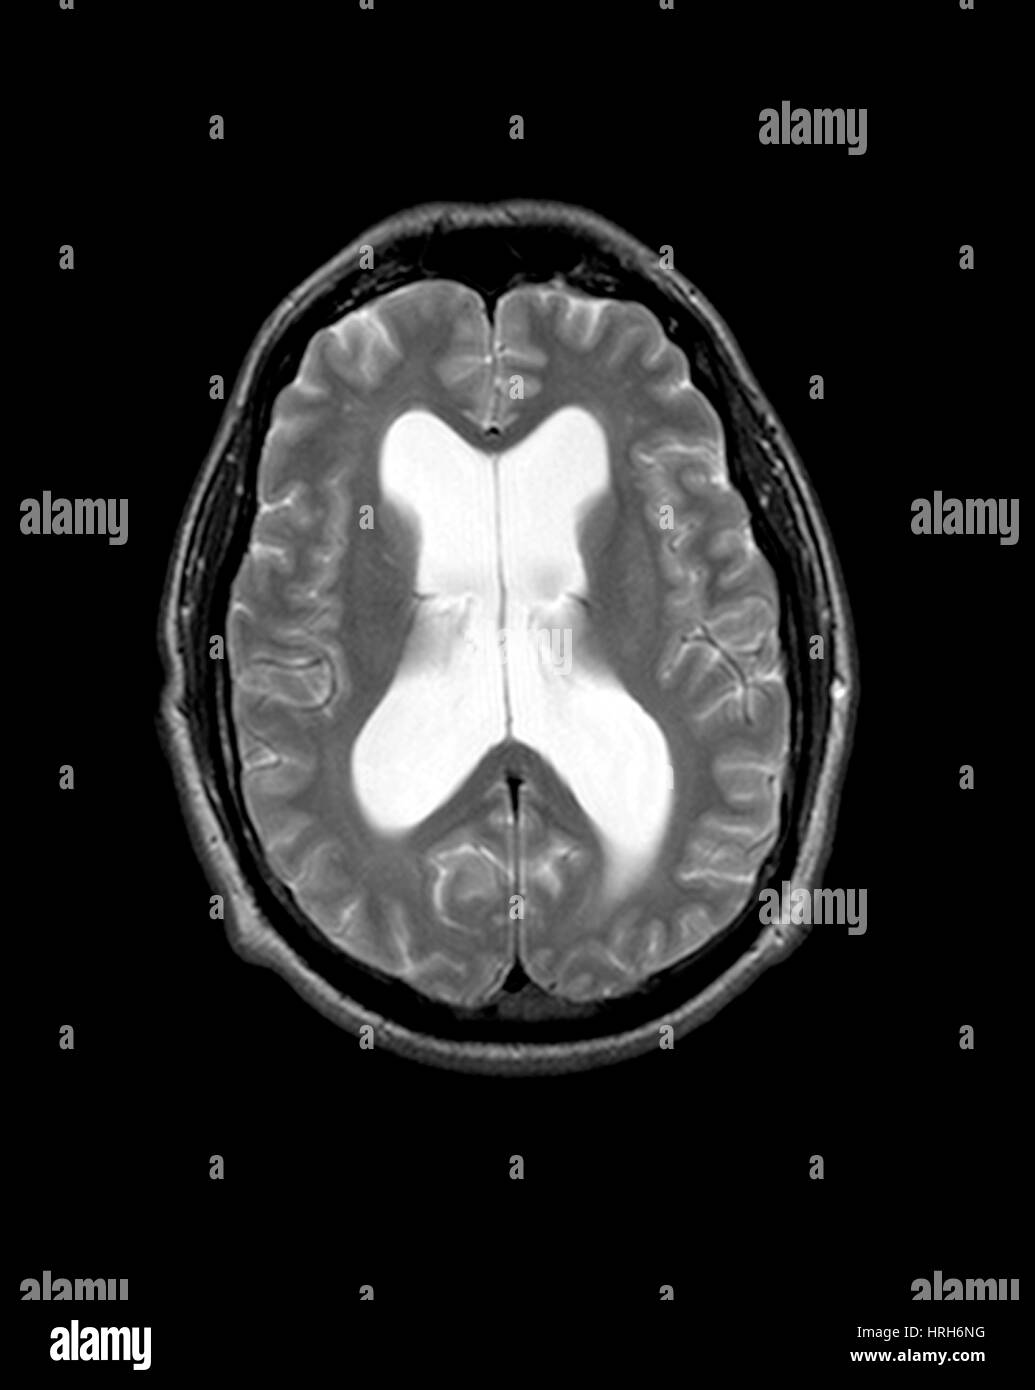

Source: terciartzsg.pages.dev Hydrocéphalie à pression normale une mise à jour Aerzteverlag medinfo AG , On imaging, it can be characterized both on CT and MRI by enlarged lateral and third ventricles out of proportion. L'incidence de l'hydrocéphalie à pression normale est de 5,5 personnes sur 100 000 par an

Hydrocéphalie à pression normale La Revue du Praticien Hydrocephalie definition traitements Trouver un établissement Rechercher un médecin Contactez-nous Trouver un Causes Dans la majorité des cas, la cause de l'hydrocéphalie à pression normale est inconnue En raison de cette accumulation, les ventricules se dilatent et peuvent endommager ou détruire les tissus cérébraux.

Source: lennixalo.pages.dev Hydrocéphalie chronique et autres pathologies chroniques du liquide cérébrospinal Fiche santé HCL , En raison de cette accumulation, les ventricules se dilatent et peuvent endommager ou détruire les tissus cérébraux. L'hydrocéphalie à pression normale (HPN) a été décrite pour la première fois en 1965 par Adams et Hakim